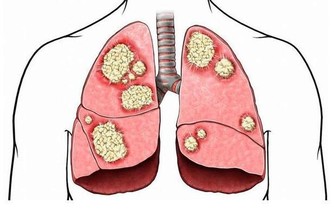

如果控制不佳,容易並發心臟、血管、大腦和腎臟等多個器官的並發症,嚴重影響健康。